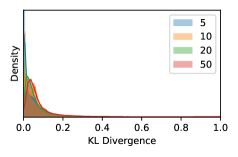

5.1 Distribution of Uncertainty Scores

Distribution of Uncertainty Scores Across Different Severity Levels As explained in Section 3, each uncertainty metric essentially defines an order/ranking among the data points. We conducted an analysis to better understand what data will be assigned high uncertainty under a particular uncertainty metric . Picking out the highest ranked data points (), we calculated the ratio of data points from each SL. Figure 4 summarizes the results as box plots for the Kaggle-DR and the Messidor-2 datasets; additional detailed statistics can be found in Table S.1 in the supplementary materials. From the plot and table, SL1 & SL2 examples account for a higher proportion among the top-ranked uncertain examples across the three ensemble methods. This finding matches our intuition that incipient disease examples (SL1 & SL2) are more likely to be considered uncertain by ensemble methods due to their ambiguity.

In contrast, the MC-dropout method showed the worst overall performance among the three, as it can be seen from the high ratios of SL0 examples among the uncertain negatives in Figure 4. The histograms in Figure 2 provides another perspective to look into the phenomenon, where a decent proportion of MC-dropout model’s predictions on SL0 inputs entailed low confidence (far from 0 or 1), which from another angle explained why MC-dropout was less specific in terms of lower FNP; many no-DR inputs (i.e. SL0) were erroneously assigned high uncertainty by MC-dropout models.

As discussed in Section 5.1 and Section 5.3 in the main paper, the mean metric and the stacking ensemble will have better performance in the precision (specificity) on the ambiguous data. Here, more detailed results are shown in Figures S.3 & S.6 and Table S.1. Figures S.3 & S.4 show the histograms of the uncertainty score for Kaggle-DR and Messidor-2 datasets that are the in-distribution (i.d.) dataset in our experiment and FigureS.5 & S.6 show the histograms for ImageNet and CIFAR-10 datasets, which is the o.o.d. datasets in our experiment. Each group of histograms contains results from the three evaluated ensemble methods (stacking ensemble, MC-dropout and TTA) and the three uncertainty metrics (mean, var and kl). Additional detailed results not displayed in Figure 4 can be found in Table S.1, which shows the proportion of the data of different SLs varies across different . For comparison, we also included in Table S.1 the results from single learners, and the proportions of data of different SLs (before any selection was made).